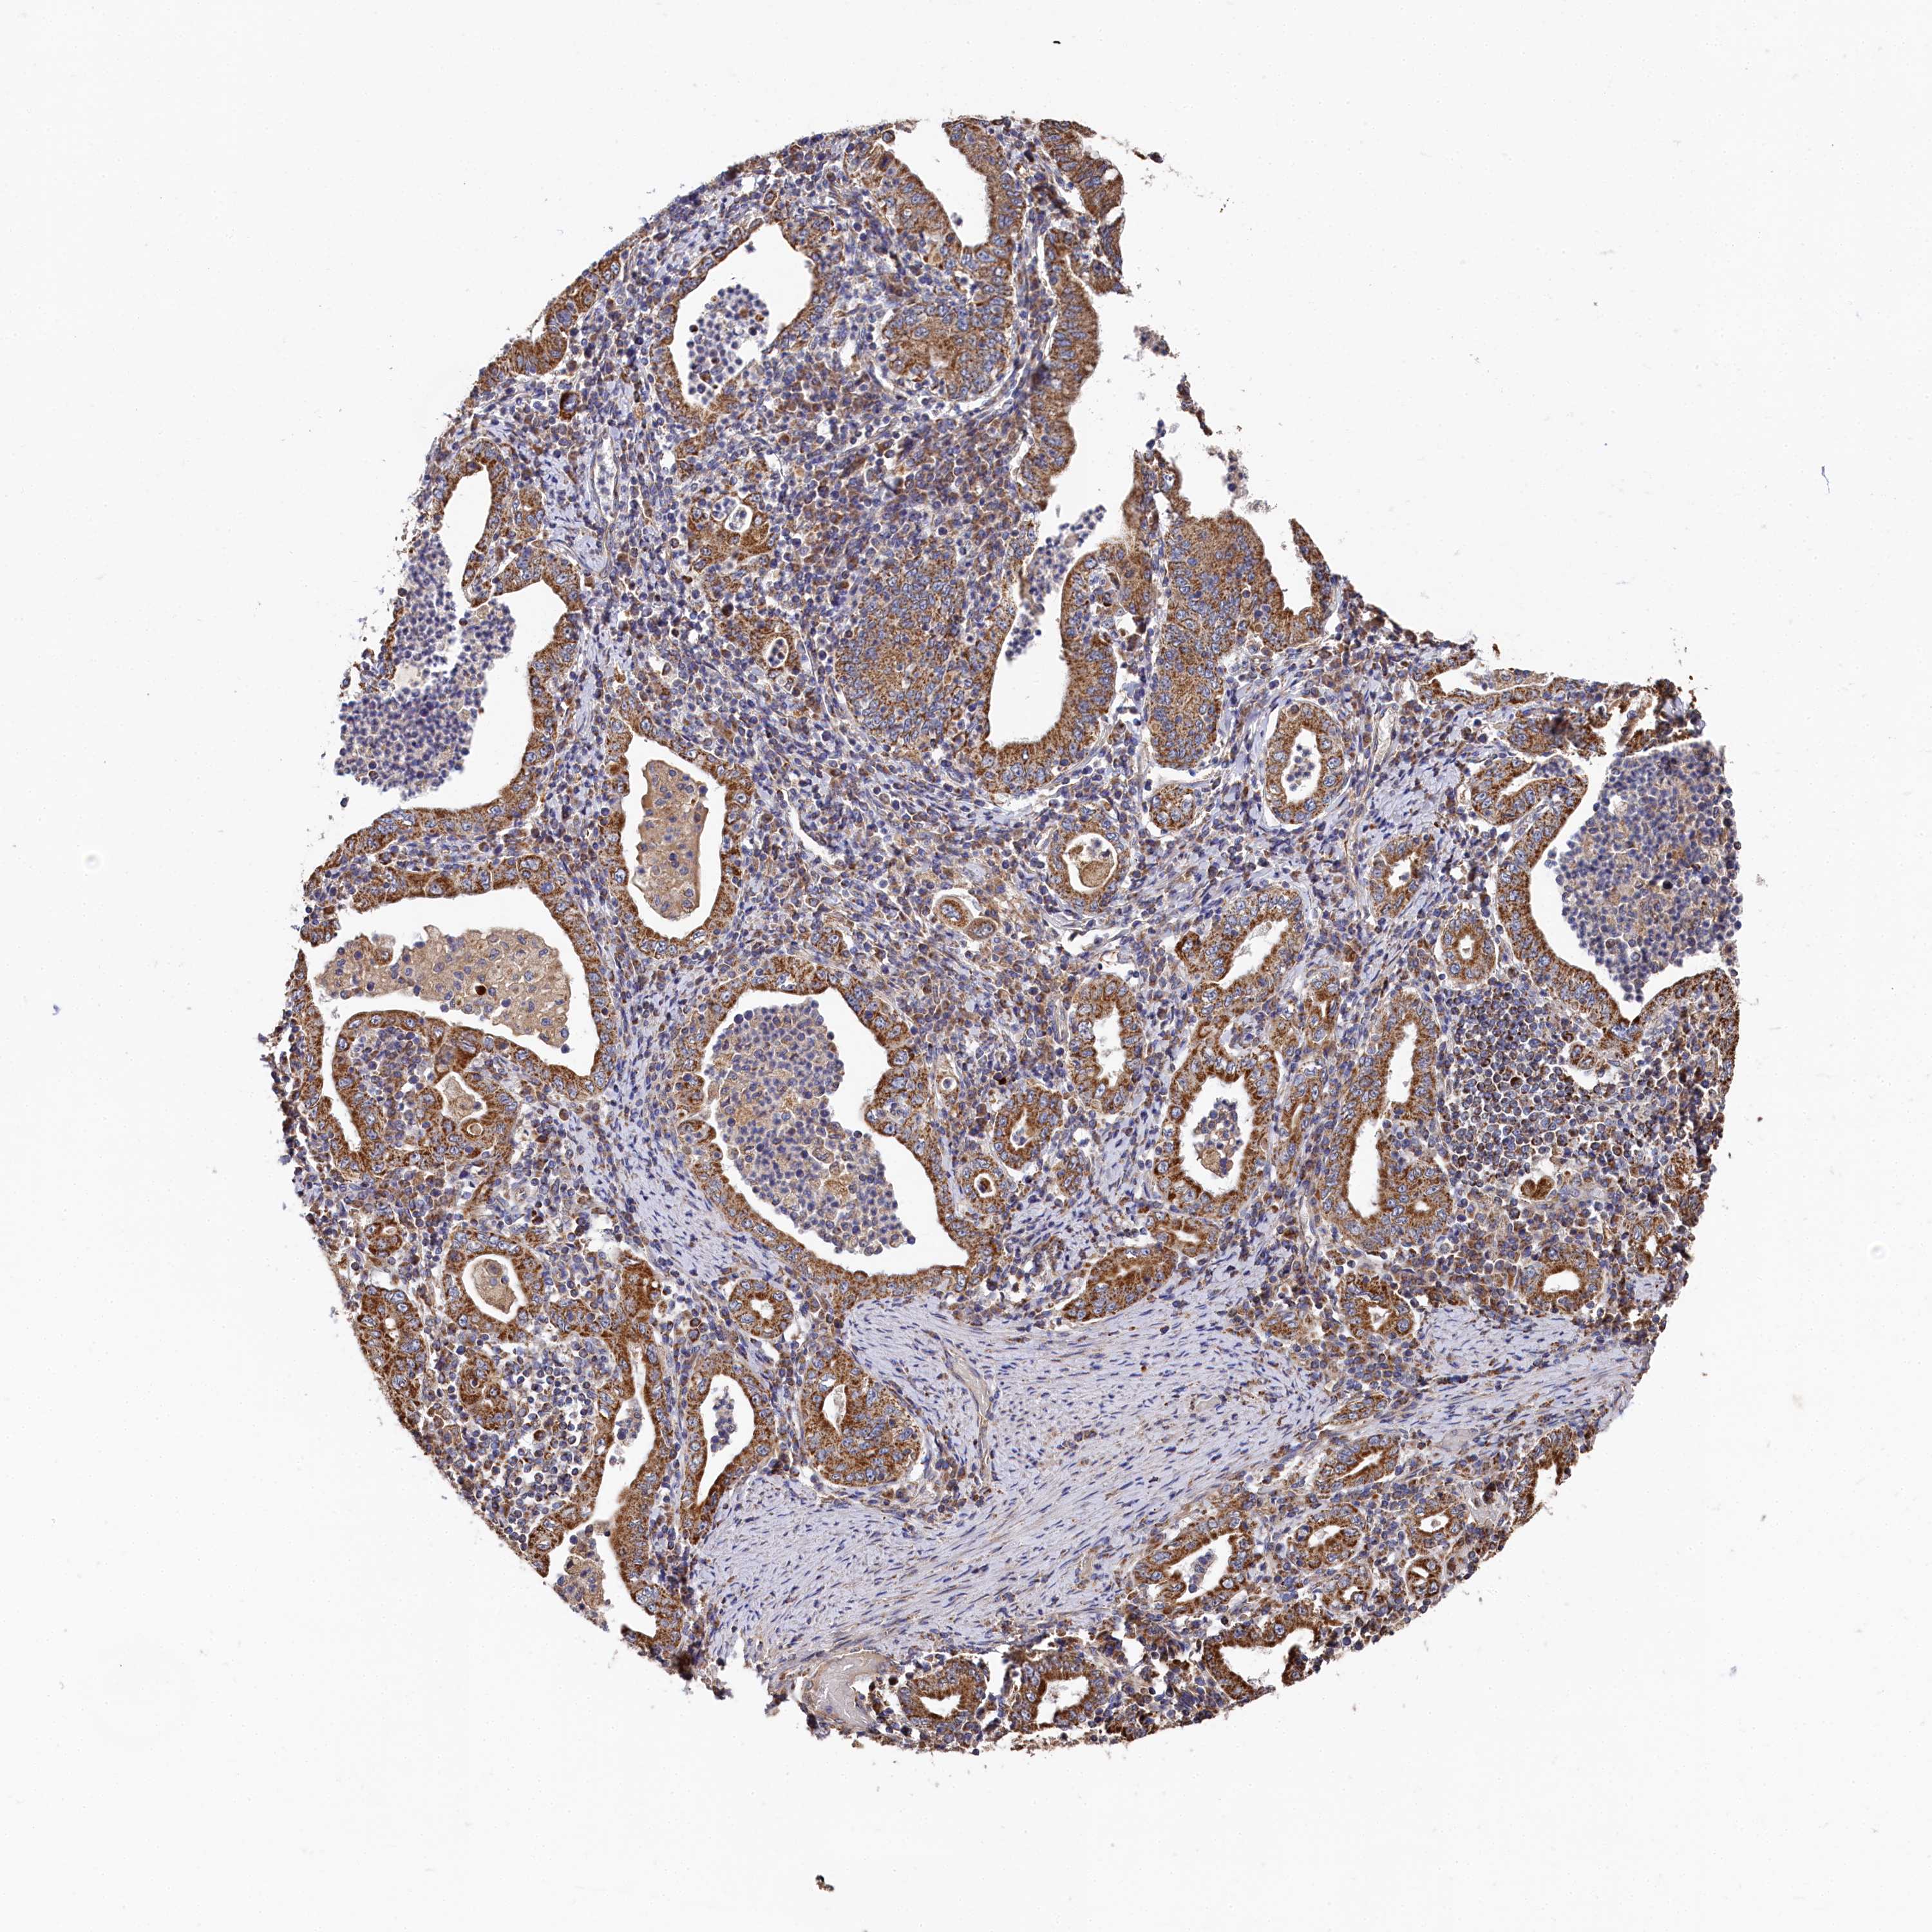

STOMACH CANCER - Protein expressioni

A mouse-over function shows sample information and annotation data. Click on an image to view it in a full screen mode. Samples can be filtered based on level of antibody staining by selecting one or several of the following categories: high, medium, low and not detected. The assay and annotation is described here.

Antibody stainingi

Antibody staining in the annotated cell types in the current human tissue is reported as not detected, low, medium, or high, based on conventional immunohistochemistry profiling in selected tissues. This score is based on the combination of the staining intensity and fraction of stained cells.

Each image is clickable and will lead to virtual microscopy that enables deeper exploration of all samples and also displays staining intensity scores, fraction scores and subcellular localization as well as patient and tissue information for each sample.

Antibody HPA039965

Staining

High

Medium

Low

Not detected

Intensity

Strong

Moderate

Weak

Negative

Quantity

>75%

75%-25%

<25%

None

Location

Nuclear

Cytoplasmic/membranous

Cytoplasmic/membranous,nuclear

Adenocarcinoma, NOS

Adenocarcinoma, High grade